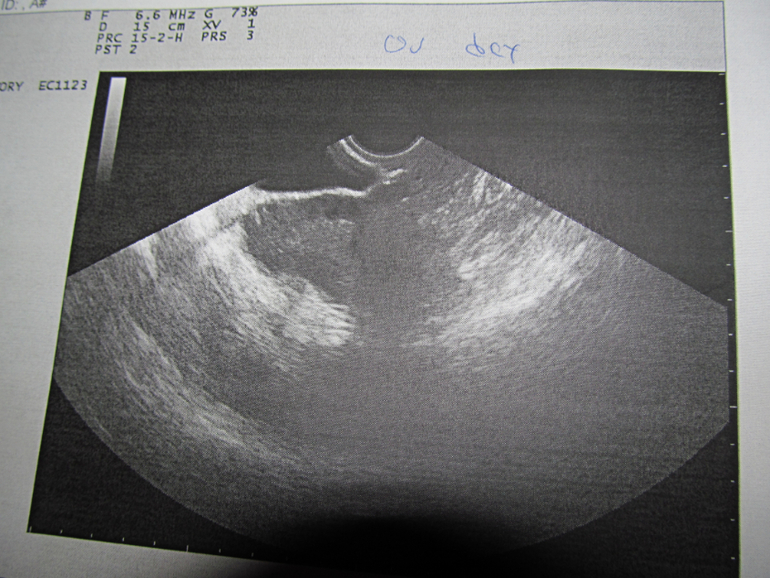

помогите расшифровать УЗИ...что можете сказать по снимкам...я только узнала матку,а что на остальных я баран..не могу понять и рассмотреть

эндометрий 15 мм...на вчерашний 24 дц...а сегодня мес начались...вообще у меня проблемы с гормонами,по этому врач мне назначил Лютеину,потому,что эндик больше 7 мм не рос и мес были раз в 2-3 месяца...очень обрадовалась,что Лютеина так мне помогла))